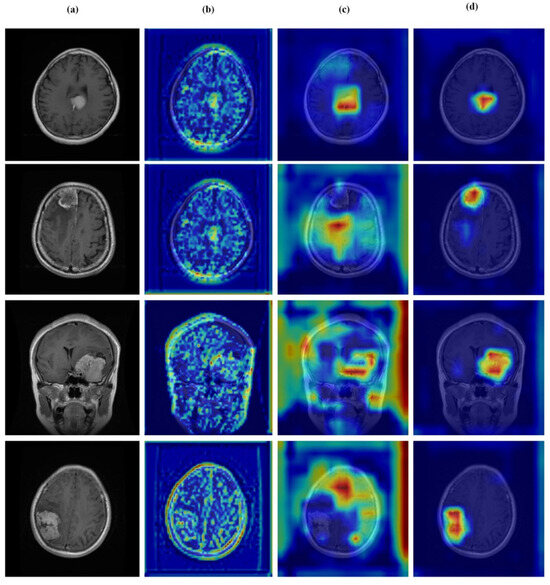

4.7. Feature Learning Analysis

Figure 12, Figure 13, Figure 14 and Figure 15 present Grad-CAM visualizations that trace the hierarchical feature learning of the proposed model across the four classes. Columns are organized as (a) input, (b) high-level features, (c) mid-level features, and (d) low-level features. In (d), the network emphasizes primitive cue edges, intensity transitions, and fine textures capturing sulcal boundaries, skull edges, and generic tissue patterns. Progressing to (c), activations become more structured and context-aware, highlighting coherent anatomical regions and diffuse hyperintense areas that provide spatial context for lesion localization. At (b), class-discriminative focus emerges with responses that contract tumor-centric hotspots for glioma and meningioma and to the sellar region for pituitary cases, while no_tumor images exhibit suppressed high-level responses, reflecting the model’s rejection of false lesion cues. This bottom-to-top progression from generic edges to task-specific evidence explains the model’s improved decision reliability and aligns with the multi-task design that encourages precise, clinically meaningful attention.

Visual representation of feature activations in pituitary tumor cases. (a) input, (b) low-level features, (c) mid-level features, and (d) high-level features.

Limitation and Future Work